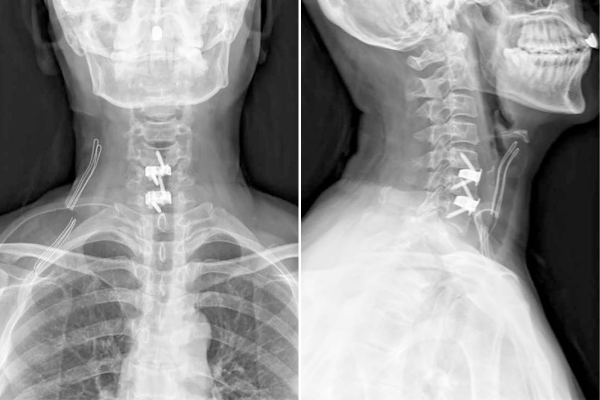

图2 双节段3D打印零切迹融合器置入术后影像

56岁的王先生因神经根型颈椎病长期饱受颈肩疼痛和右手拇指麻木的困扰,保守治疗无效后,接受了3D打印零切迹融合器手术。术后第一天,他的疼痛和麻木症状明显缓解,术后第三天便顺利出院。王先生表示:“手术效果立竿见影,恢复速度远超预期!”一周后,贺永雄团队又为一名两节段颈椎病患者成功实施手术(图2),术后患者颈肩痛和右前臂、手指麻木症状明显改善。